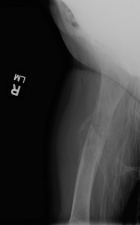

Patient is a 6 y/o female who presented w/ R. thigh pain and inability to bear wt. after attempting to stand for seated position

She c/o R. knee pain for several months w/ fevers and increased inflammatory markers w/ presumed dx. of JRA; PMH: unremarkable

PE: R. thigh swollen/warm with TTP; NVI